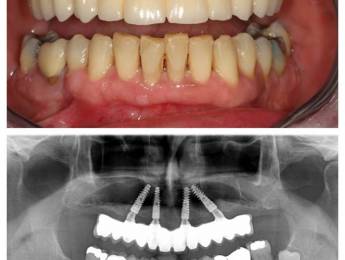

All-on-4 előtte-utána

Először helyi érzéstelenítést adunk, majd 4 titánium implantátumot helyezünk be. Kettőt egyenesen az állcsont elülső és kettőt ferdén a hátsó területére. Ezek fogják támasztani az állkapocsba rögzített teljes hidat. Az így behelyezett híd természetesnek hat, hosszú ideig jól illeszkedik, nem mozog, ezáltal garantálja a természetes fogak funkcionalitását és harapási minőségét.